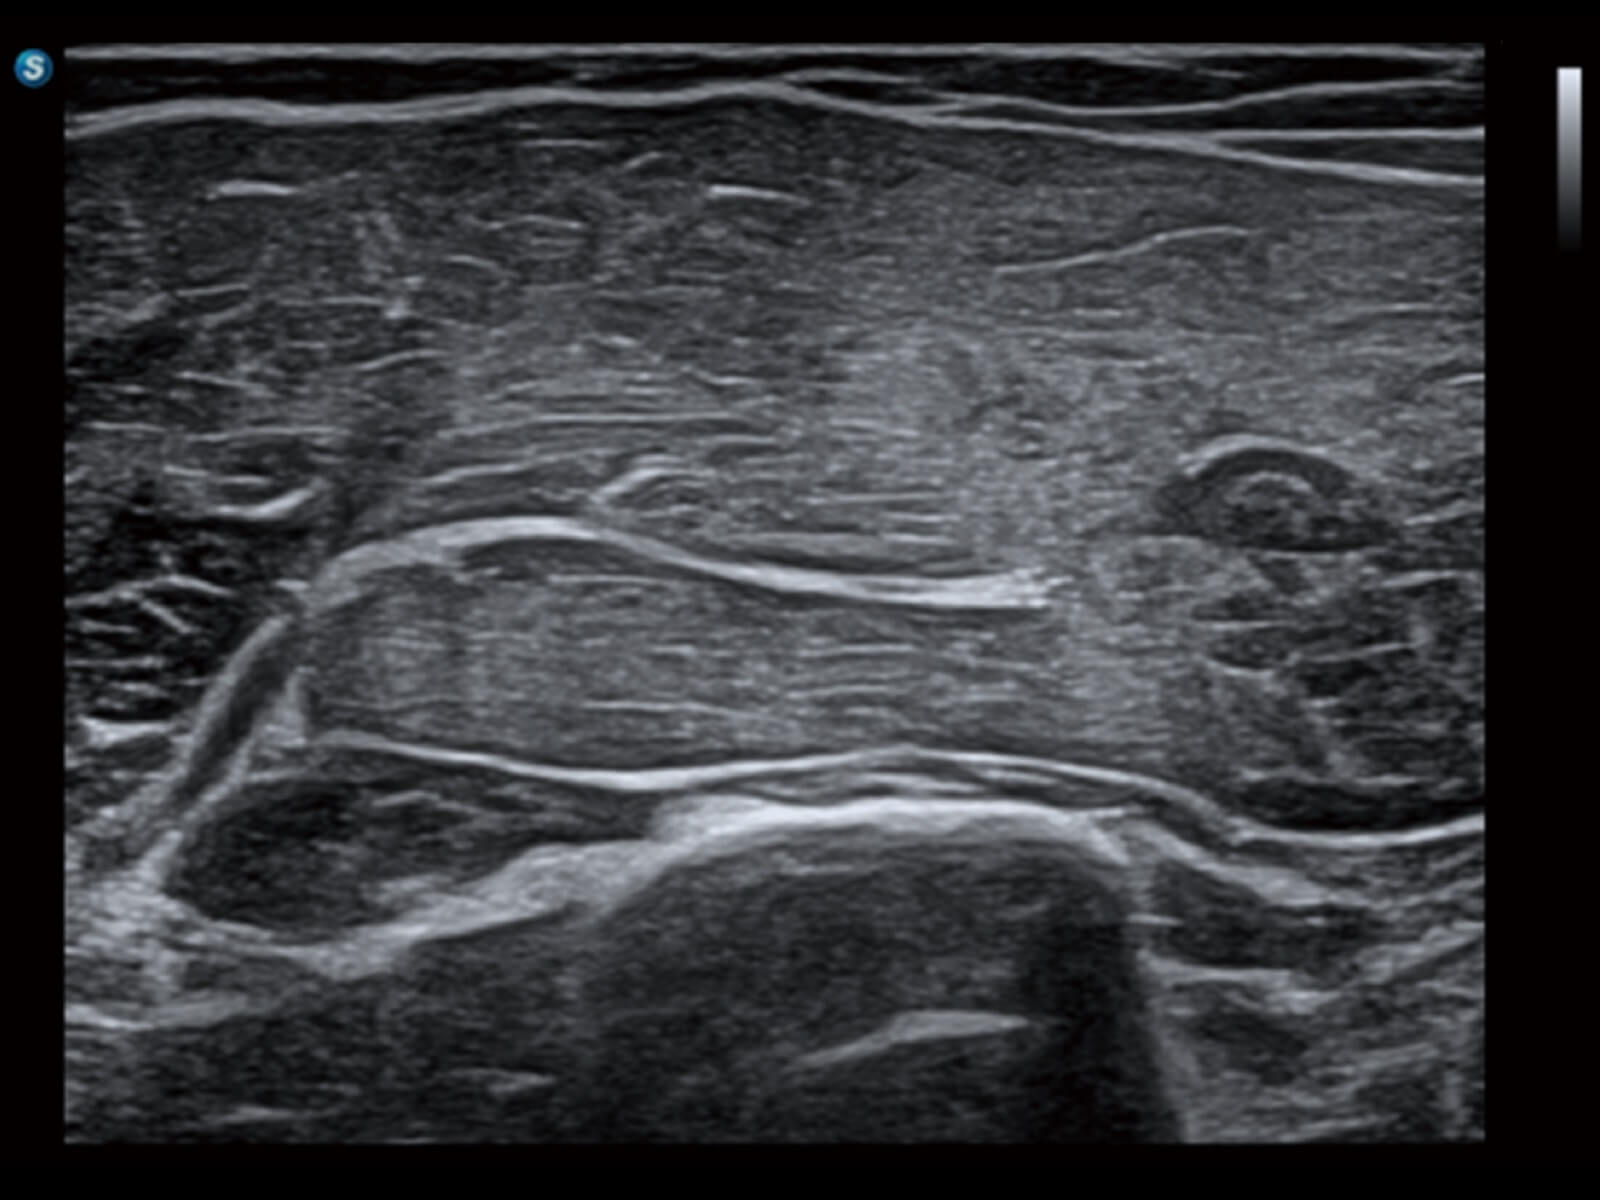

肌骨